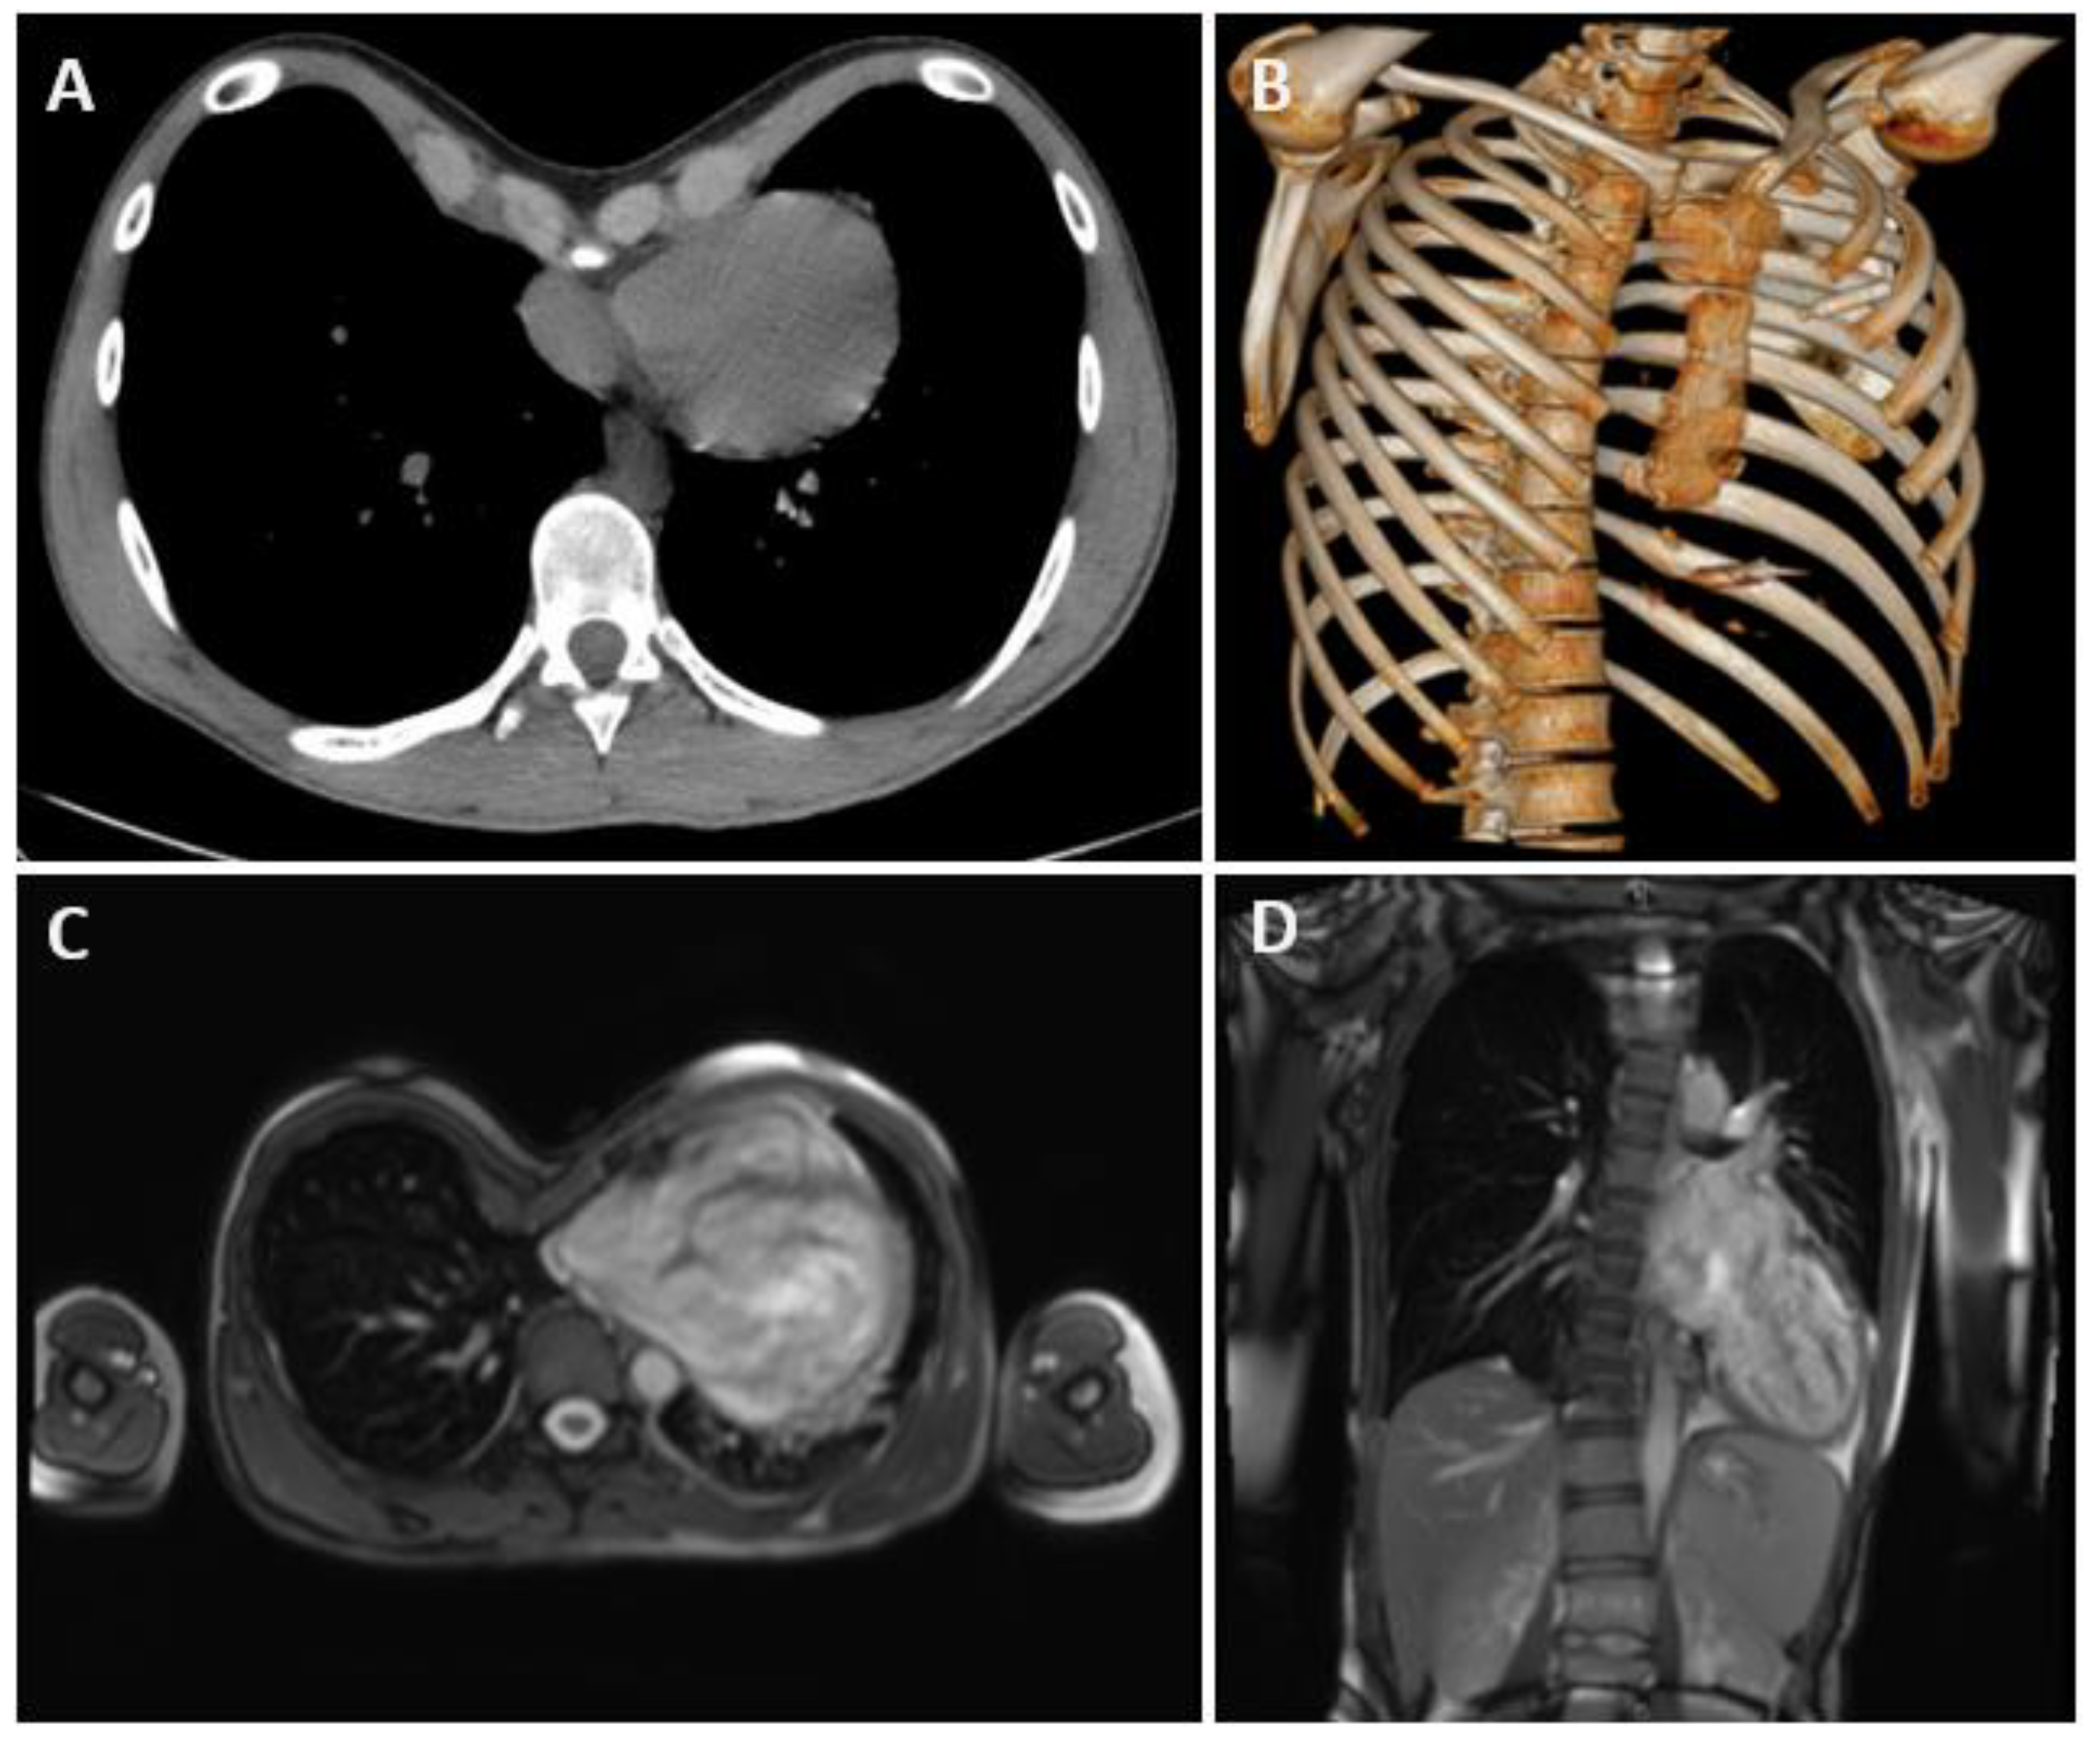

| 1 | 16 | 5 | VF arrest | S-ICD | 3 | - |

| 2 | 15 | 6.8 | MVP | - | 3 | MS, Scoliosis, PA |